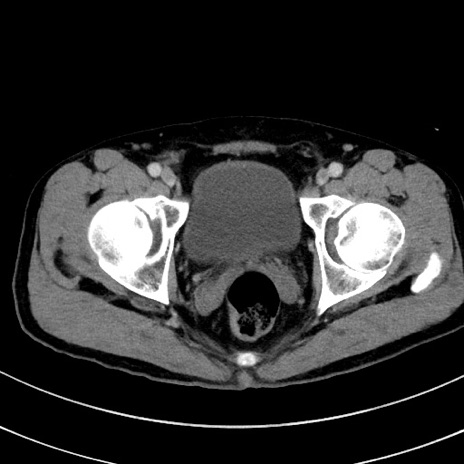

症例8(横断像)

【症例】 60歳代男性

【主訴】 黒色吐物

【現病歴】 4日前から嘔気自覚、2日前の朝食後にも嘔気あり、自分で手で嘔吐反射起こし嘔吐したところ血が混ざっていたため受診。

【既往歴】 5年前汎発性腹膜炎を伴う急性虫垂炎で手術、高血圧、前立腺肥大症、高脂血症

【身体所見】 腹部正中に手術癩痕あり 腹部平坦・軟圧痛なし膨満感あり

【データ】WBC 8400、CRP 4.54